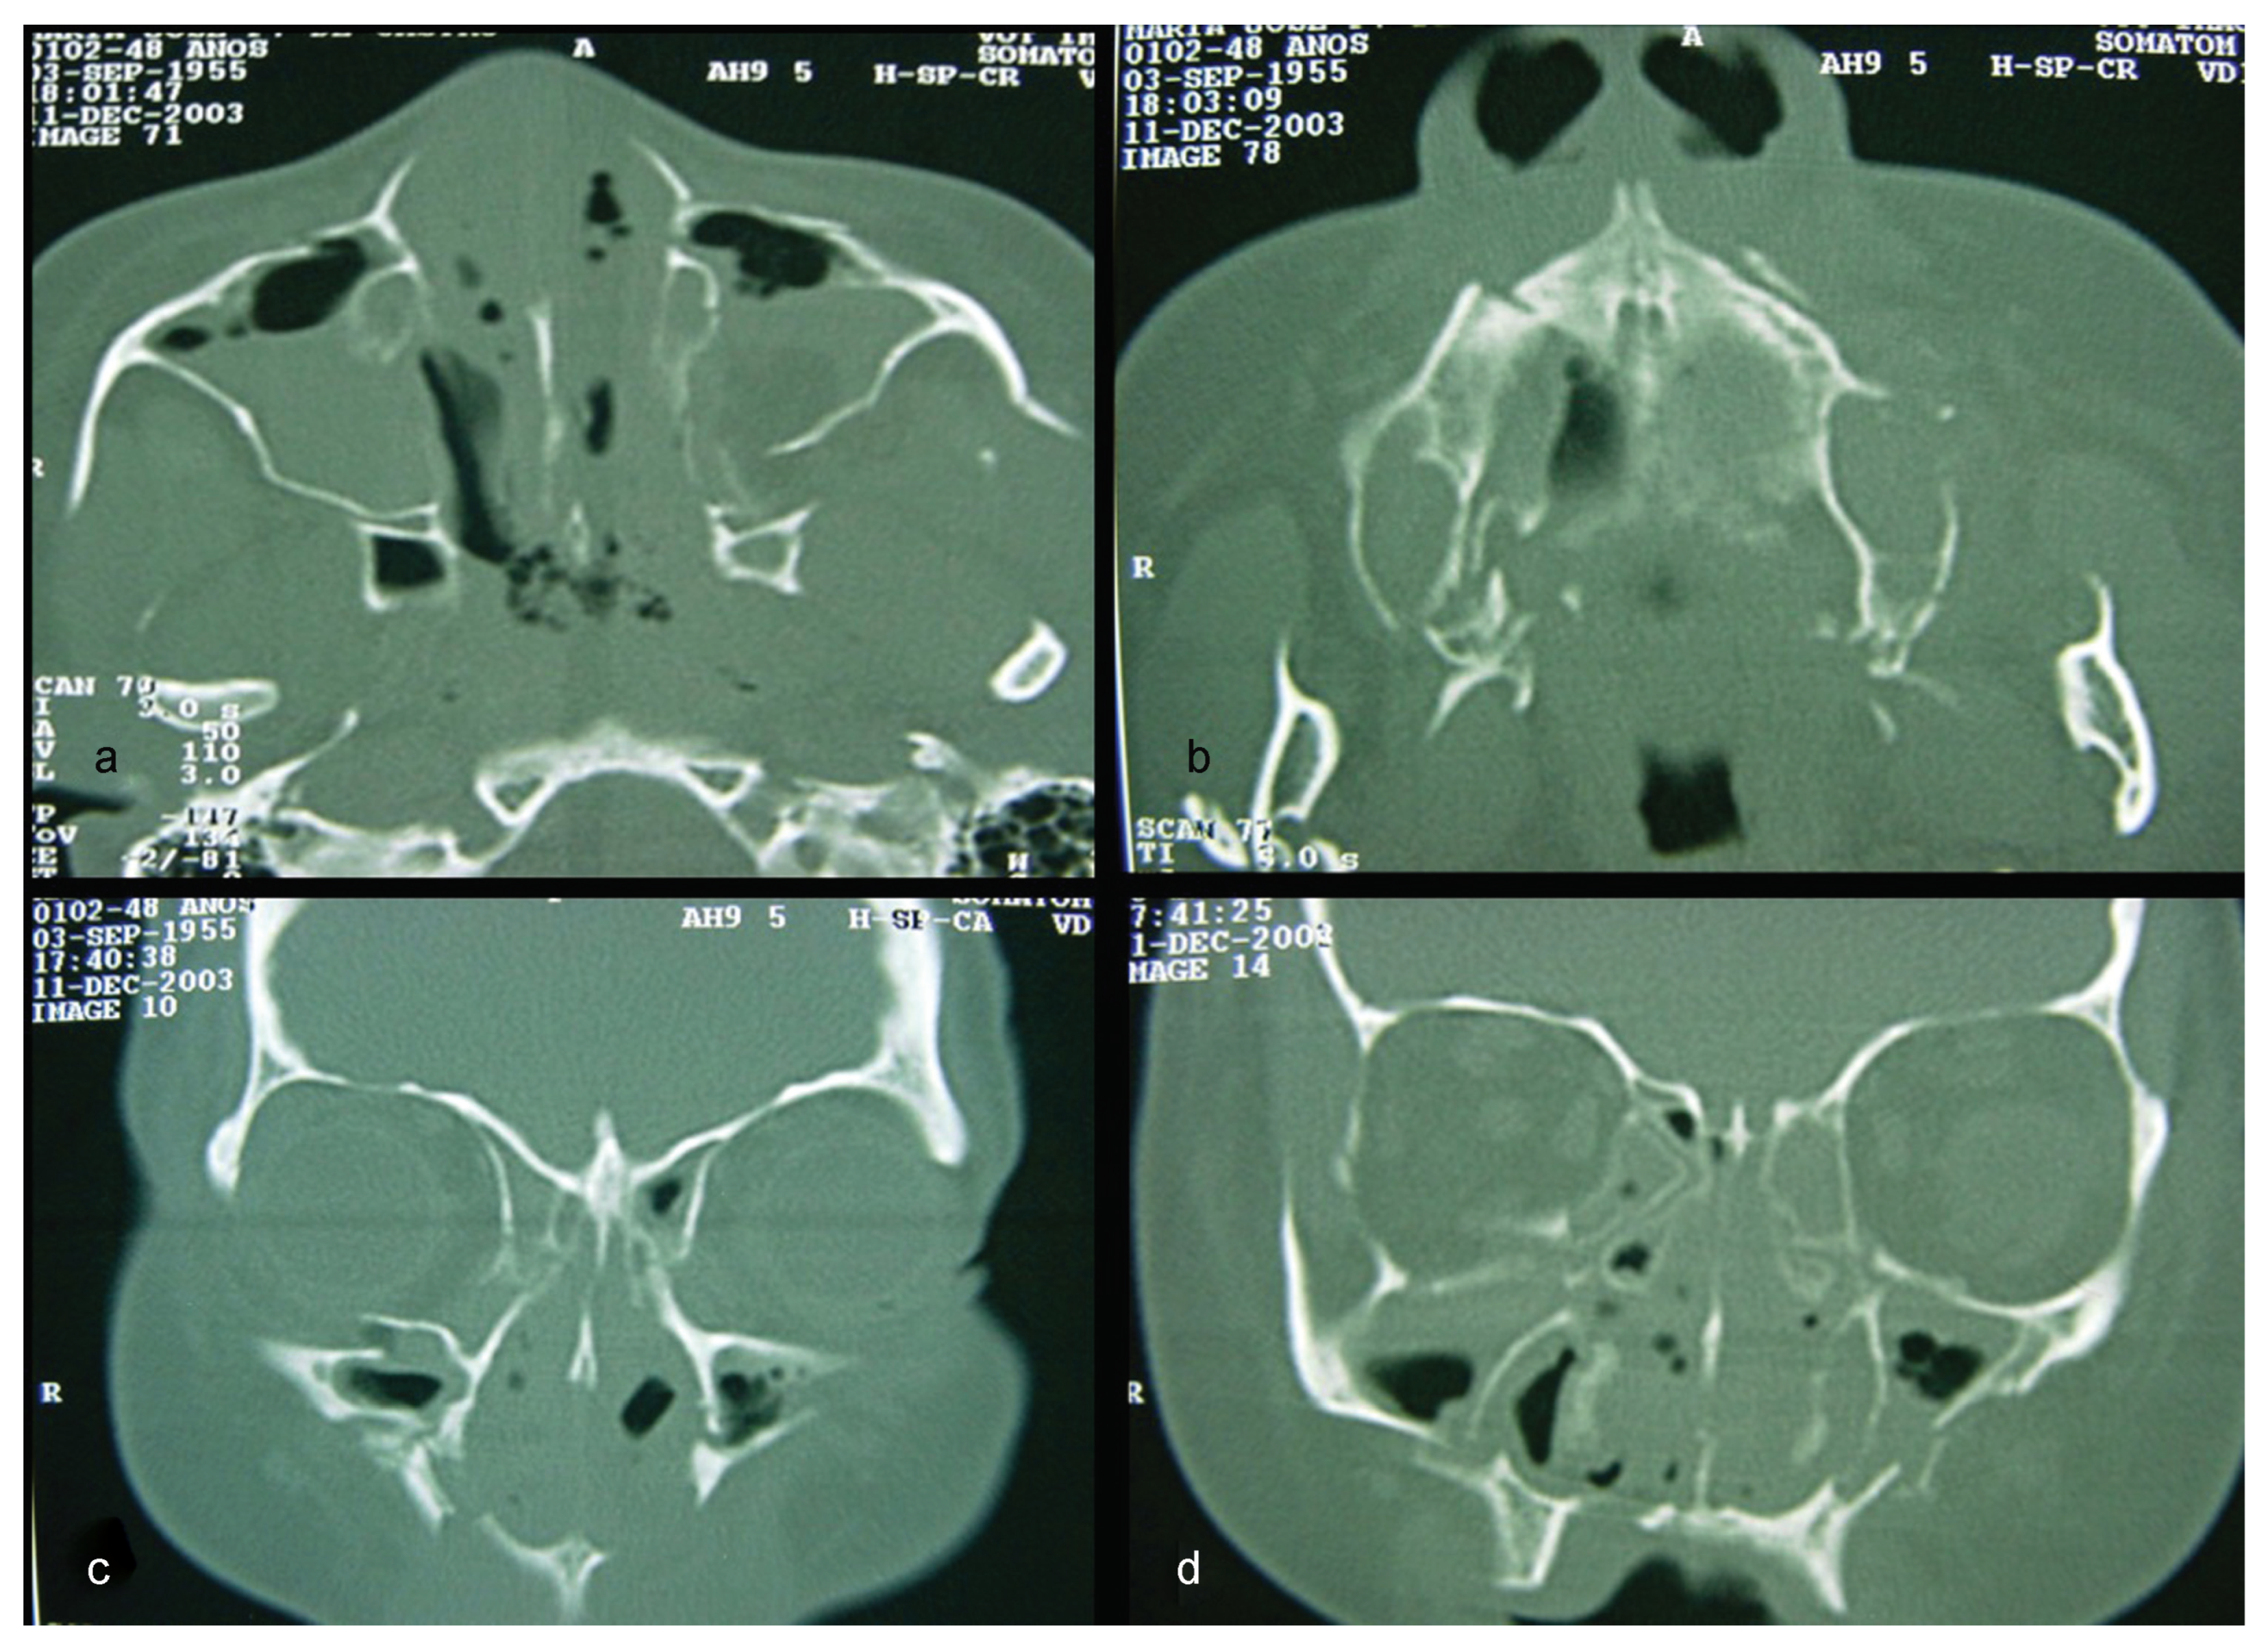

A computed tomography (CT) was performed in a fourchannel spiral CT scanner (Toshiba Asteion 4; Toshiba, Tokyo, Japan) with axial, coronal, and sagittal views. Multiple frac-tures were identified on the face (Figure 2 and Figure 3) and on the left side of the SS region (Figure 4).

Figure 3. CT windows displaying multiple fractures in the lower third of the face or mandibular region.

Figure 4. CT windows with arrows highlighting fractures to the sphenoidal sinus.